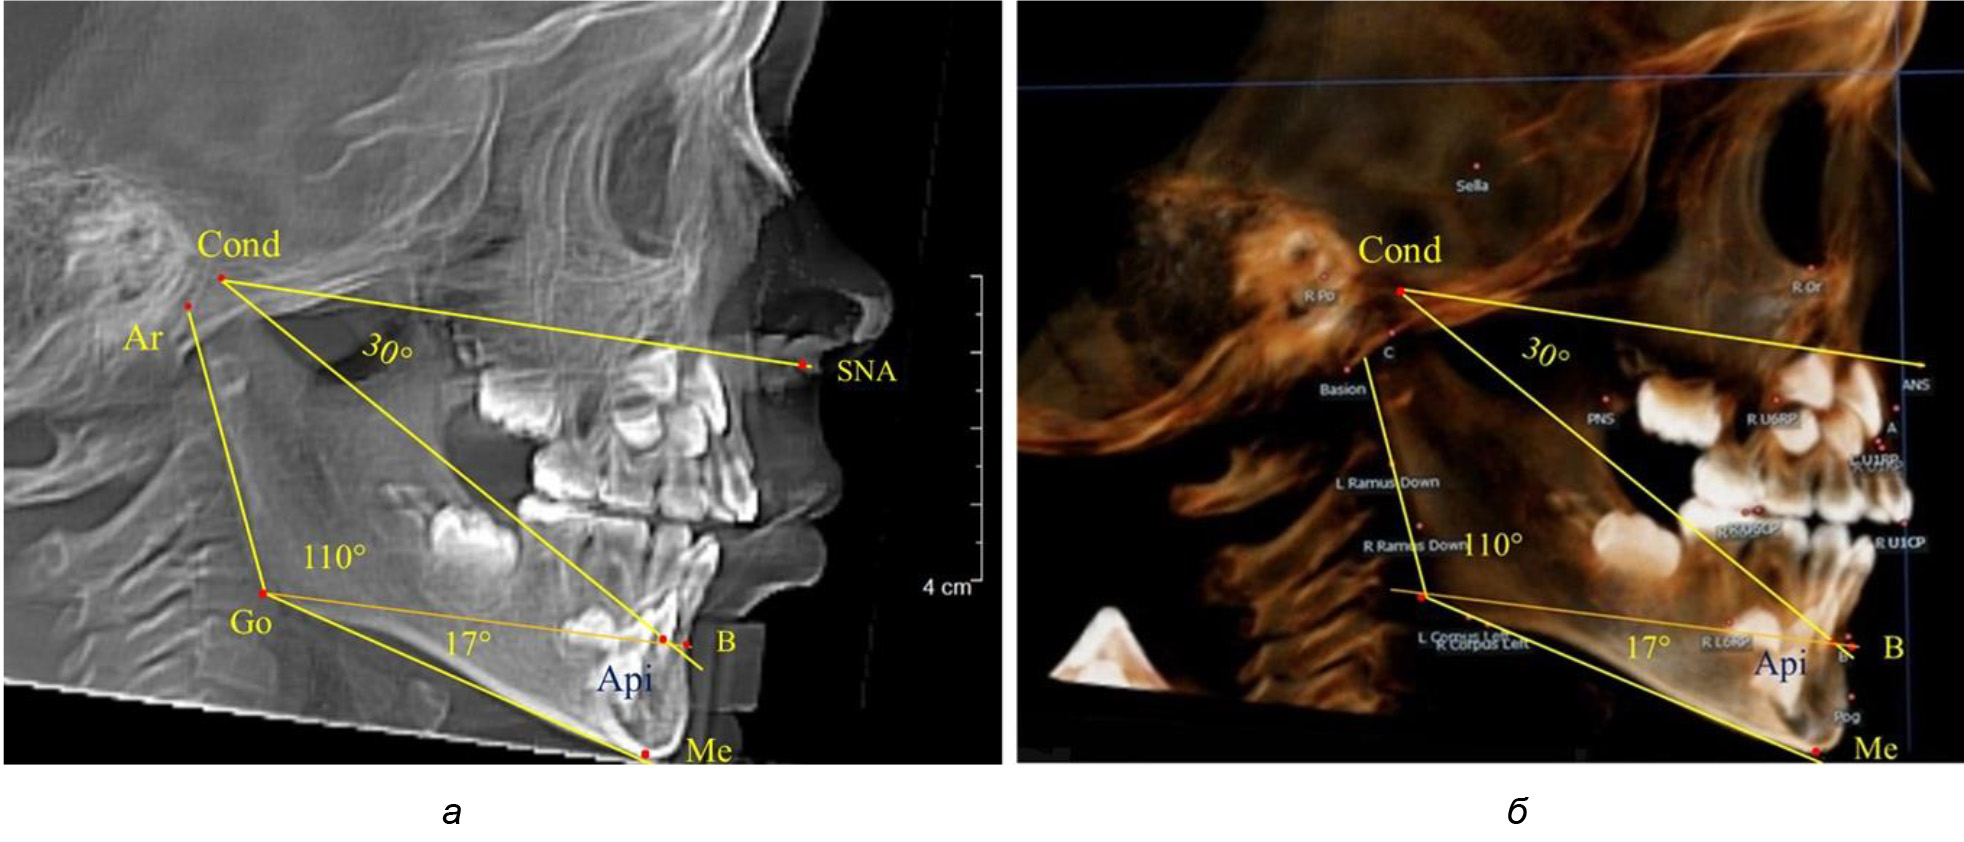

При анализе ТРГ 5 детей в периоде прикуса молочных зубов отмечено, что величина основного угла гнатической части лица SNA-Cond-Api, как правило, в норме составляла около 30°, и его величина была относительно стабильной у всех обследованных детей. В то же время угол нижней челюсти и его составляющие отличались вариабельностью параметров при различных показателях нижнечелюстного угла (рис. 4).

Рис. 4. Особенности ТРГ (а) и 3D-модели (б) в периоде прикуса молочных зубов

Таким образом, в периоде молочного прикуса с оптимальными окклюзионными соотношениями, несмотря на линейные размеры в вертикальном и сагиттальном направлении, которые, безусловно, меньше параметров взрослых людей, величина основного угла гнатической части лица SNA-Cond-Api соответствовала параметрам людей с полностью сформированным физиологическим прикусом постоянных зубов. Анализируя данные рентгенограмм детей в периоде сменного прикуса, отмечено, что величина основного угла гнатической части лица SNA-Cond-Api, так же как в молочном и постоянном прикусе, в норме составляла от 28 до 32°. В то же время угол нижней челюсти и его составляющие отличались вариабельностью параметров при различных показателях нижнечелюстного угла. Достоверных различий угла гнатической части после смены нижних медиальных резцов и прорезывания первых постоянных моляров (4 ребенка) не было; происходил очередной этап подъема высоты прикуса и увеличение линейных размеров костей гнатической части, однако угловые параметры были относительно стабильны. После смены всех резцов и замены первых молочных моляров первыми премолярами (6 человек) увеличивались линейные размеры при сохранившихся угловых показателях гнатической части лица (рис. 5).

Рис. 5. Варианты ТРГ после прорезывания ППМ и нижних резцов (а), всех резцов и первых премоляров (б)